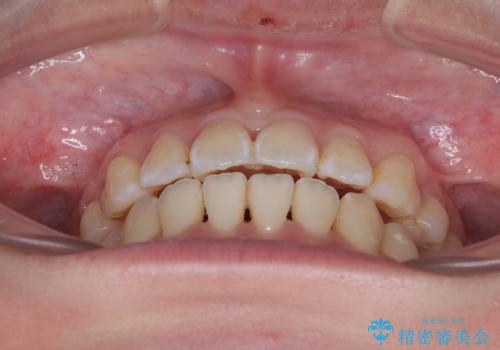

- 上下の出っ歯を気にして来院された患者様です。

口元を積極的に引っ込めるために、上下左右の第一小臼歯を4本抜歯することとしました。

また、上下前歯は舌の突出癖による開咬となっていたため、舌のトレーニングを徹底するよう指示しました。

舌突出癖の改善トレーニングは、仕上がり、治療期間、そして治療後の後戻りに大きな影響を及ぼします。

トレーニングをしっかりと行っていただいたため、スッキリとした口元に仕上がりました。